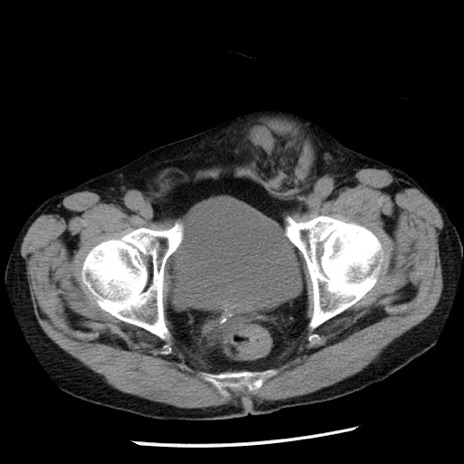

症例26(横断像)

【症例】80歳代男性

【主訴】嘔吐

【現病歴】昨晩2回嘔吐あり、今朝になっても嘔吐あり。来院。

【既往歴】胃潰瘍

【身体所見】意識清明、BT 37.6℃、BP 166/95mmHg、HR 100bpm、SpO2 97%、腹部:平坦・軟、腸蠕動音聴取良好、圧痛なし。

【データ】WBC 21900、CRP 1.46